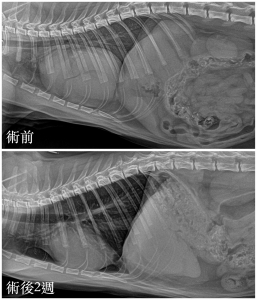

手術順利完成後,兩週複診X 光追蹤,可見心臟、肺臟與肝臟位置都恢復正常,小貓也恢復得很好喔